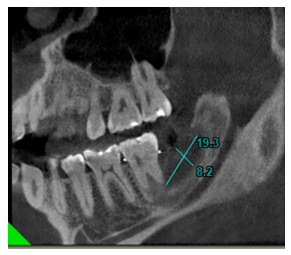

En el corte oblicuo se observó una imagen hiperdensa compatible con crecimiento óseo siendo en unidades métricas desde el borde anterior de la mandíbula hacia la basal mandibular de 8.2 mm y en sentido postero-anterior de 19.3 mm. Siendo evidente la ganancia ósea en relación con el primer control radiográfico.

Figura 13 Corte de tomografía computarizada de haz cónico, en donde se evidencia en vista oblicua una imagen hiperdensa compatible con crecimiento óseo. medidas referenciales 8.2 mm x 19.3 mm. Fuente: Historia Clínica. Especialización Cirugía Bucal ULAC-IDOLA. 2022